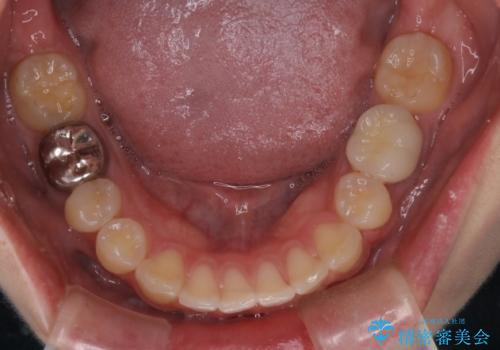

出っ歯の矯正 抜歯をしてしっかり引っ込めるワイヤー矯正

- 治療計画

- 出っ歯を気にして来院されました。

しっかり前歯を下げるために抜歯を合計3本行いワイヤーにて矯正を行う計画としました。

見た目もよくなり、口も閉じるようになったと満足していただけました。

予定よりも早く終了することができたことにも喜んでいただけました。